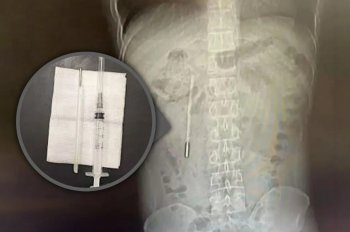

Un bărbat care acuza dureri abdominale a descoperit la spital că avea în corp un termometru înghițit în urmă cu 20 de ani

Un bărbat din China în vârstă de 32 de ani a ajuns la spital...